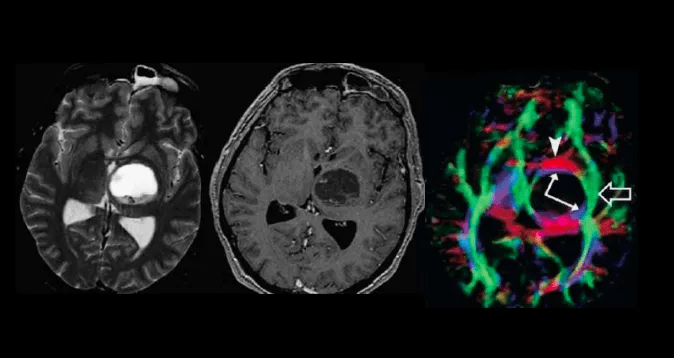

头颅磁共振dwi高信号一定就是脑梗死吗?